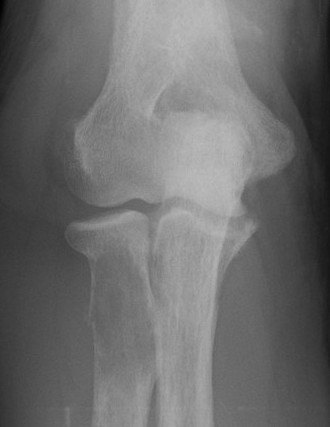

X-ray

Eccentric, sharply demarcated lytic lesion

- no sclerosis around lesion

- narrow zone of transition

- metaphysis, extending into epiphysis

- no mineralization

85% meta-epiphysis of long bones